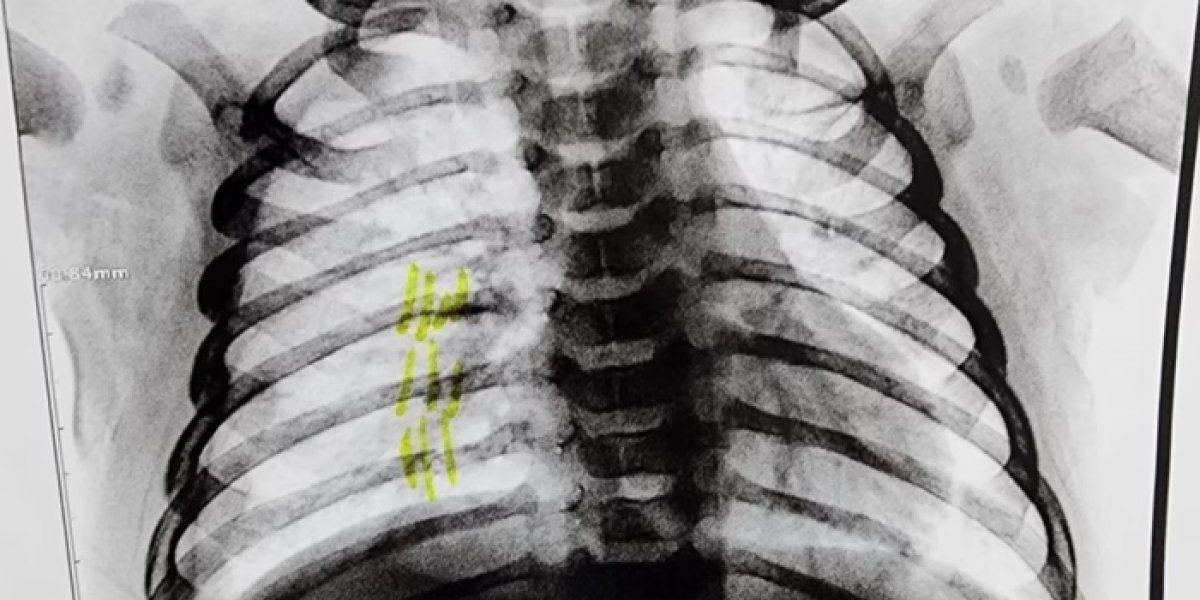

“A criança passou por radiografia que constatou três costelas quebradas, bem quebradas. Até quem não é médico olha ali e sabe que está quebrado. Juntando com as lesões externas, ficou bem caracterizado que foi uma agressão. Um espancamento”, afirmou o delegado.